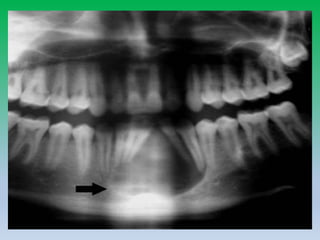

• 42-year-old woman

with periapicalcyst.

• Cropped panoramic

radiograph shows

radiolucent

lesion(arrowhead) in

posterior body of

ramus of mandible

with displacement of

mandibular canal

(arrow).